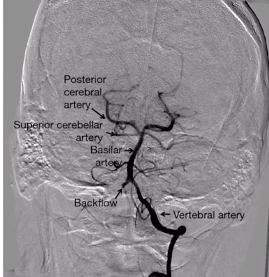

label A-D [4]

A: vertebral artery

B: superior cerebellar artery

C: posterior cerebral artery

D: basilar artery